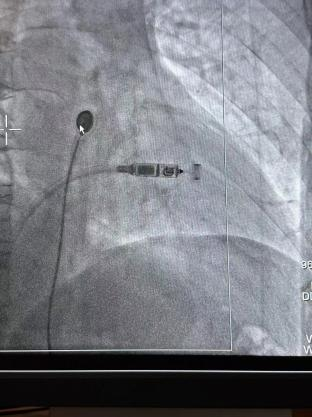

術(shù)前準(zhǔn)備充分后,李大爺在局部麻醉下行無(wú)導(dǎo)線心臟起搏器植入。心血管內(nèi)科醫(yī)生從大爺大腿根部?jī)H穿刺一個(gè)米粒粗細(xì)的小口,通過導(dǎo)管將起搏器植入心腔內(nèi)。該手術(shù)1個(gè)小時(shí)即順利完成,手術(shù)過程中大爺完全清醒,幾乎無(wú)疼痛感覺。

據(jù)悉,Micra無(wú)導(dǎo)線起搏器被稱為“全球最小的心臟起搏器”,其體積相比傳統(tǒng)心臟起搏器減小93%,重量約傳統(tǒng)起搏器的1/10。

該術(shù)式經(jīng)穿刺后直接植入在心腔內(nèi),無(wú)需在胸前皮下制作囊袋。無(wú)傷疤、無(wú)切口,患者恢復(fù)時(shí)間快,減少了創(chuàng)傷與感染風(fēng)險(xiǎn),大大改善了患者的生存質(zhì)量。